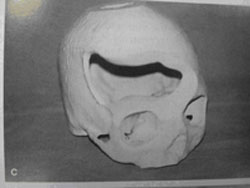

图5 头颅冠状位CT

(来自plastic and reconstructive surgery)